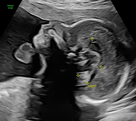

Ersttrimesterscreening

Das Ersttrimesterscreening ist die erste große Ultraschalluntersuchung in der Schwangerschaft und findet zwischen 12.-14. Schwangerschaftswoche statt.

Teil der Untersuchung ist einerseits die Berechnung eines individuellen Risikos für die häufigsten Chromosomenstörungen – Trisomie 21 (Down Syndrom), Trisomie 18 (Edwards Syndrom) und Trisomie 13 (Pätau Syndrom). Das Risiko wird Anhand des Alters der Patientin und spezifischen Ultraschallmarkern (Nackentransparenz, Nasenknochen, spezifische Blutflussmuster) berechnet.

Zudem werden die Entwicklung des Kindes und seine Organe untersucht. Dabei wird  großen Wert auf das kindliche Herz gelegt, denn viele Herzfehler können bereits zu diesem frühen Zeitpunkt erkannt werden, obwohl das Herz zu diesem Zeitpunkt erst so groß ist wie ein Reiskorn.

Das Ersttrimsesterscreening kann mit einem Nicht-invasiven Bluttest für Chromosomenstörungen kombiniert werden. (s. Abschnitt NIPT)

Der Vorteil des Ertstrimesterscreenings ist die frühe Entdeckung von angeborenen Entwicklungsstörungen. Bei optimalen Sichtbedingungen können die Ärzte einen Großteil der Fehlbildungen schon im 1. Trimester sehen. Durch das Entdecken von Auffälligkeit in diesem sehr frühen Stadium der Schwangerschaft haben die Eltern ausreichend Zeit, um sich von den erfahrenen Ärzten der Praxis, Humangenetikern, Kinderärzten, Kinderchirurgen, Kinderkardiologen und weiteren Spezialisten beraten lassen und dann die richtigen Entscheidungen über den weiteren Schwangerschaftsverlauf zu treffen.

Besonders sinnvoll ist das Ersttrimesterscreening bei Risikoschwangerschaften (Diabetes, Bluthochdruck, Autoimmunerkrankungen, Mehrlinge etc.) Hier lassen sich zudem die Risiken für eine Frühgeburt oder eine hypertensive Schwangerschaftserkrankung (Schwangerschaftsvergiftung) individuell abschätzen und noch im ersten Trimester einen „Fahrplan“ für die Schwangerschaft erstellen.